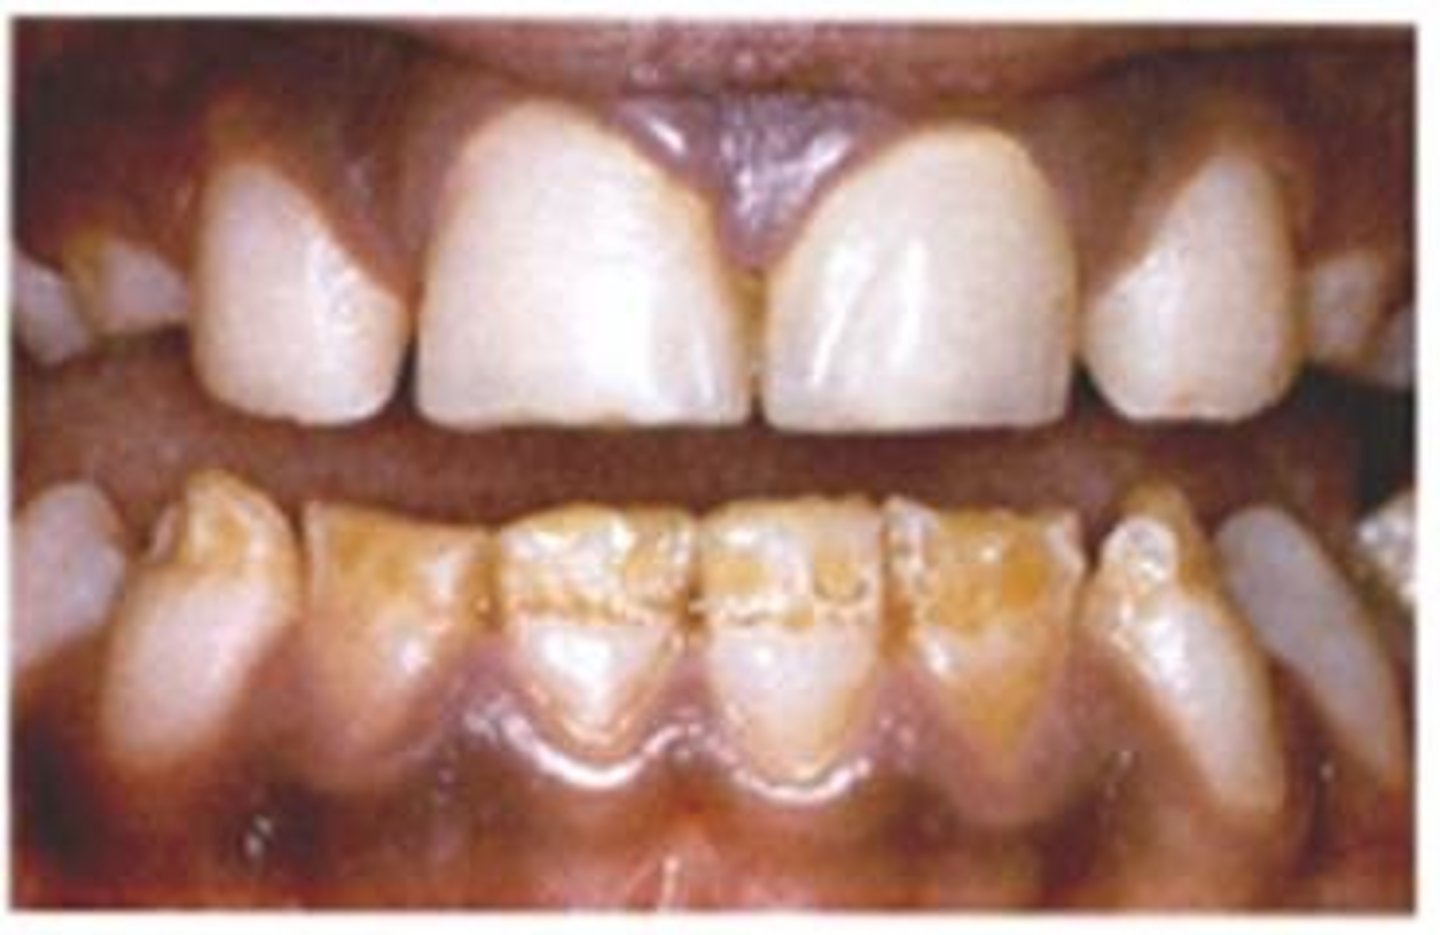

Clinical picture of 14 y.o. with inflamed gingival

Leukemia

Leukemia because high WBC, sore lymph nodes, and painful gums (they give example of 14 y.o pt. w/ inflamed gingiva)